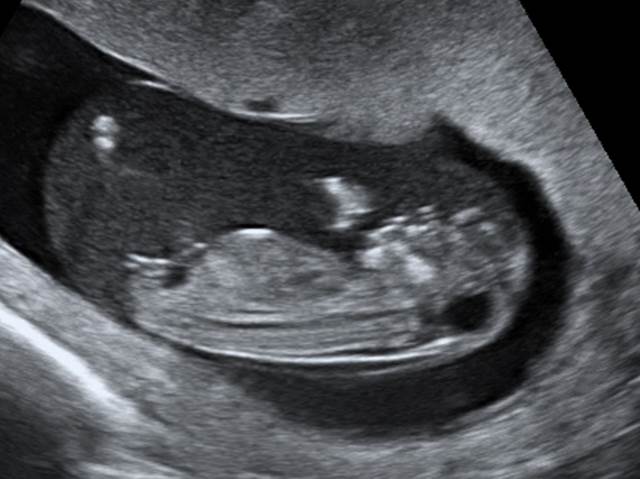

- Вашему вниманию будет представлено 7 очередных клинических задач, посвященных порокам незакрытия невральной трубки.

Вопрос 1

- Какую патологию мы можем подозревать?

- Какой дифференциальный ряд в поиске?